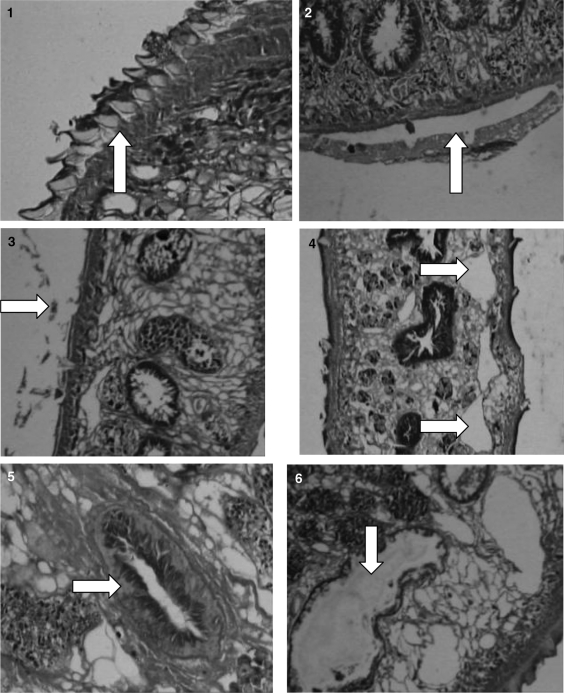

The flukes showed the normal microscopic structure of various organs and tegument in control group (Figs. 1, 5). Vacuole formation was noticed in the longitudinal section of fluke in oxyclozanide treated group (Fig. 4). Testes were massively degenerated and also there was disruption of villi in 5% oxyclozanide treated fluke. At 2.5 and 1% concentration, there was vacuolation in parenchyma, degeneration of testes, disruption of villi, but in a less intensive manner. There was complete desquamation of gut epithelial cells in flukes at 5 percent concentration of O. ficus indica (Fig. 6), whereas no changes were noticed in 2.5 and 1 percent concentration. Blebbing of the tegument was noticed in flukes treated with 5 percent concentration of A. sativum (Fig. 2). Treated fluke with 2.5 and 1 percent were normal. Detachment of spines in flukes at 5% concentration of Lawsonia was seen (Fig. 3). But no abnormality could be detected at 2.5 and 1 percent treated flukes.

Figs. 1–6.

1. Control fluke showing tegument with spines. 2. 5% Allium sativum treated fluke showing blebbing of tegument. 3. 5% Lawsonia inermis showing detachment of spines. 4. Vacuole formation in 5% oxyclozanide treated flukes. 5. Intestinal caeca with villi of control fluke. 6. 5% Opuntia treated fluke showing extensive degeneration of gut epithelium